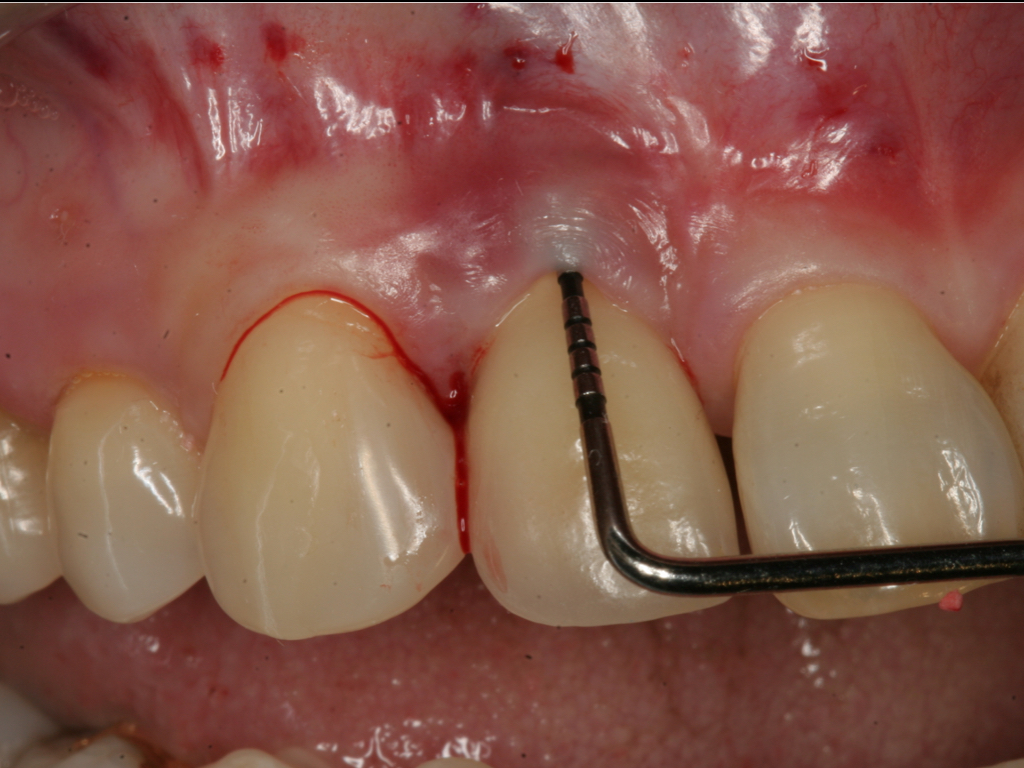

Probing is useful to determine the presence of biological complications at the buccal and lingual sites of implants, which cannot be evaluated on a radiograph (Figure 6 through Figure 8). Because of the absence of a periodontal ligament, bone loss on the buccal and lingual aspects of an implant indicates loss of support for the implant and may be a sign of additional circumferential bone loss around the implant.35

Fig 7. Probing of the buccal surface reveals additional loss of attachment around the dental implant.

Fig 8. Flap elevation confirms circumferential bone loss.

Figure 8